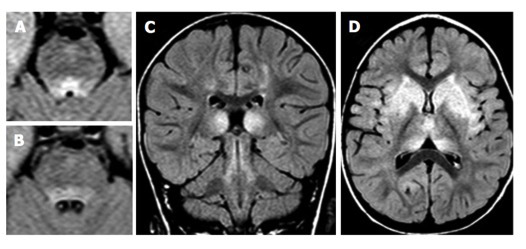

血管畸形有四種類型,動靜脈畸形,海綿狀血管瘤,毛細血管擴張和靜脈發(fā)育性異常。實質性海綿狀血管瘤MRI典型的表現(xiàn)為爆米花樣、邊界清晰、輪廓規(guī)整的復雜病變,中心區(qū)域由信號混雜灶組成,代表不同階段的出血,其周見低信號環(huán)環(huán)繞,代表含鐵血黃素沉積。

(圖 A 為靜脈血管瘤及海綿狀血管瘤;圖 B 為海綿狀血管瘤(爆米花征);圖 C 為毛細血管擴張;圖 D 為動靜脈畸形)

6、腦干發(fā)育靜脈畸形:常見于20~50 歲;大多數(shù)無癥狀,有時與癲癇、頭痛、神經功能缺損或腦積水相關,但很少出現(xiàn)破裂或出血。典型影像學表現(xiàn):海蛇頭。

7、腦干海綿狀血管瘤:一次發(fā)病多在 30 歲左右,易出血(每年增加 2.4%~6%)及再出血(21%~60%),典型影像學表現(xiàn):「桑葚樣」或「爆米花樣」。

8、腦干毛細血管擴張:大多數(shù)無癥狀,是否與臨床表現(xiàn)相關不明確;病灶大部分位于腦橋,單一,小病灶(通常小于 2 cm),大多數(shù)在 T1 相正常,T2WI 等信號或稍高信號,均勻強化或點綴樣強化;強化灶邊界不規(guī)則,刷樣改變,而并無特異性;特征性影像學表現(xiàn)為 T2*GE 序列毛細血管擴張。其它影像學表現(xiàn)包括:無占位效應,隨訪病灶穩(wěn)定。

9、腦干動靜脈畸形:原發(fā)性腦內動靜脈畸形少見,常見20~30 歲,易出血,80%~90% 的患者因顱內出血而就診,在腦干部位好發(fā)中腦,其次為腦橋及延髓;腦干部位 AVM 與顱內 AVM 影像學表現(xiàn)一致;異常擴張、發(fā)育血管結構,「流空」現(xiàn)象,有時因血管內高流速或血栓形成可呈高信號,AVM 破裂時可有出血征象。